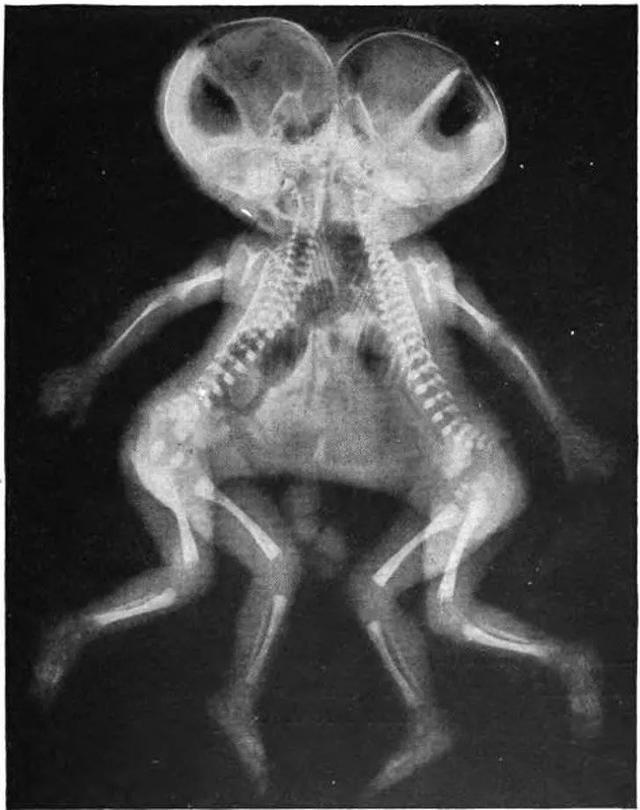

一对连体双胞胎

![]() |